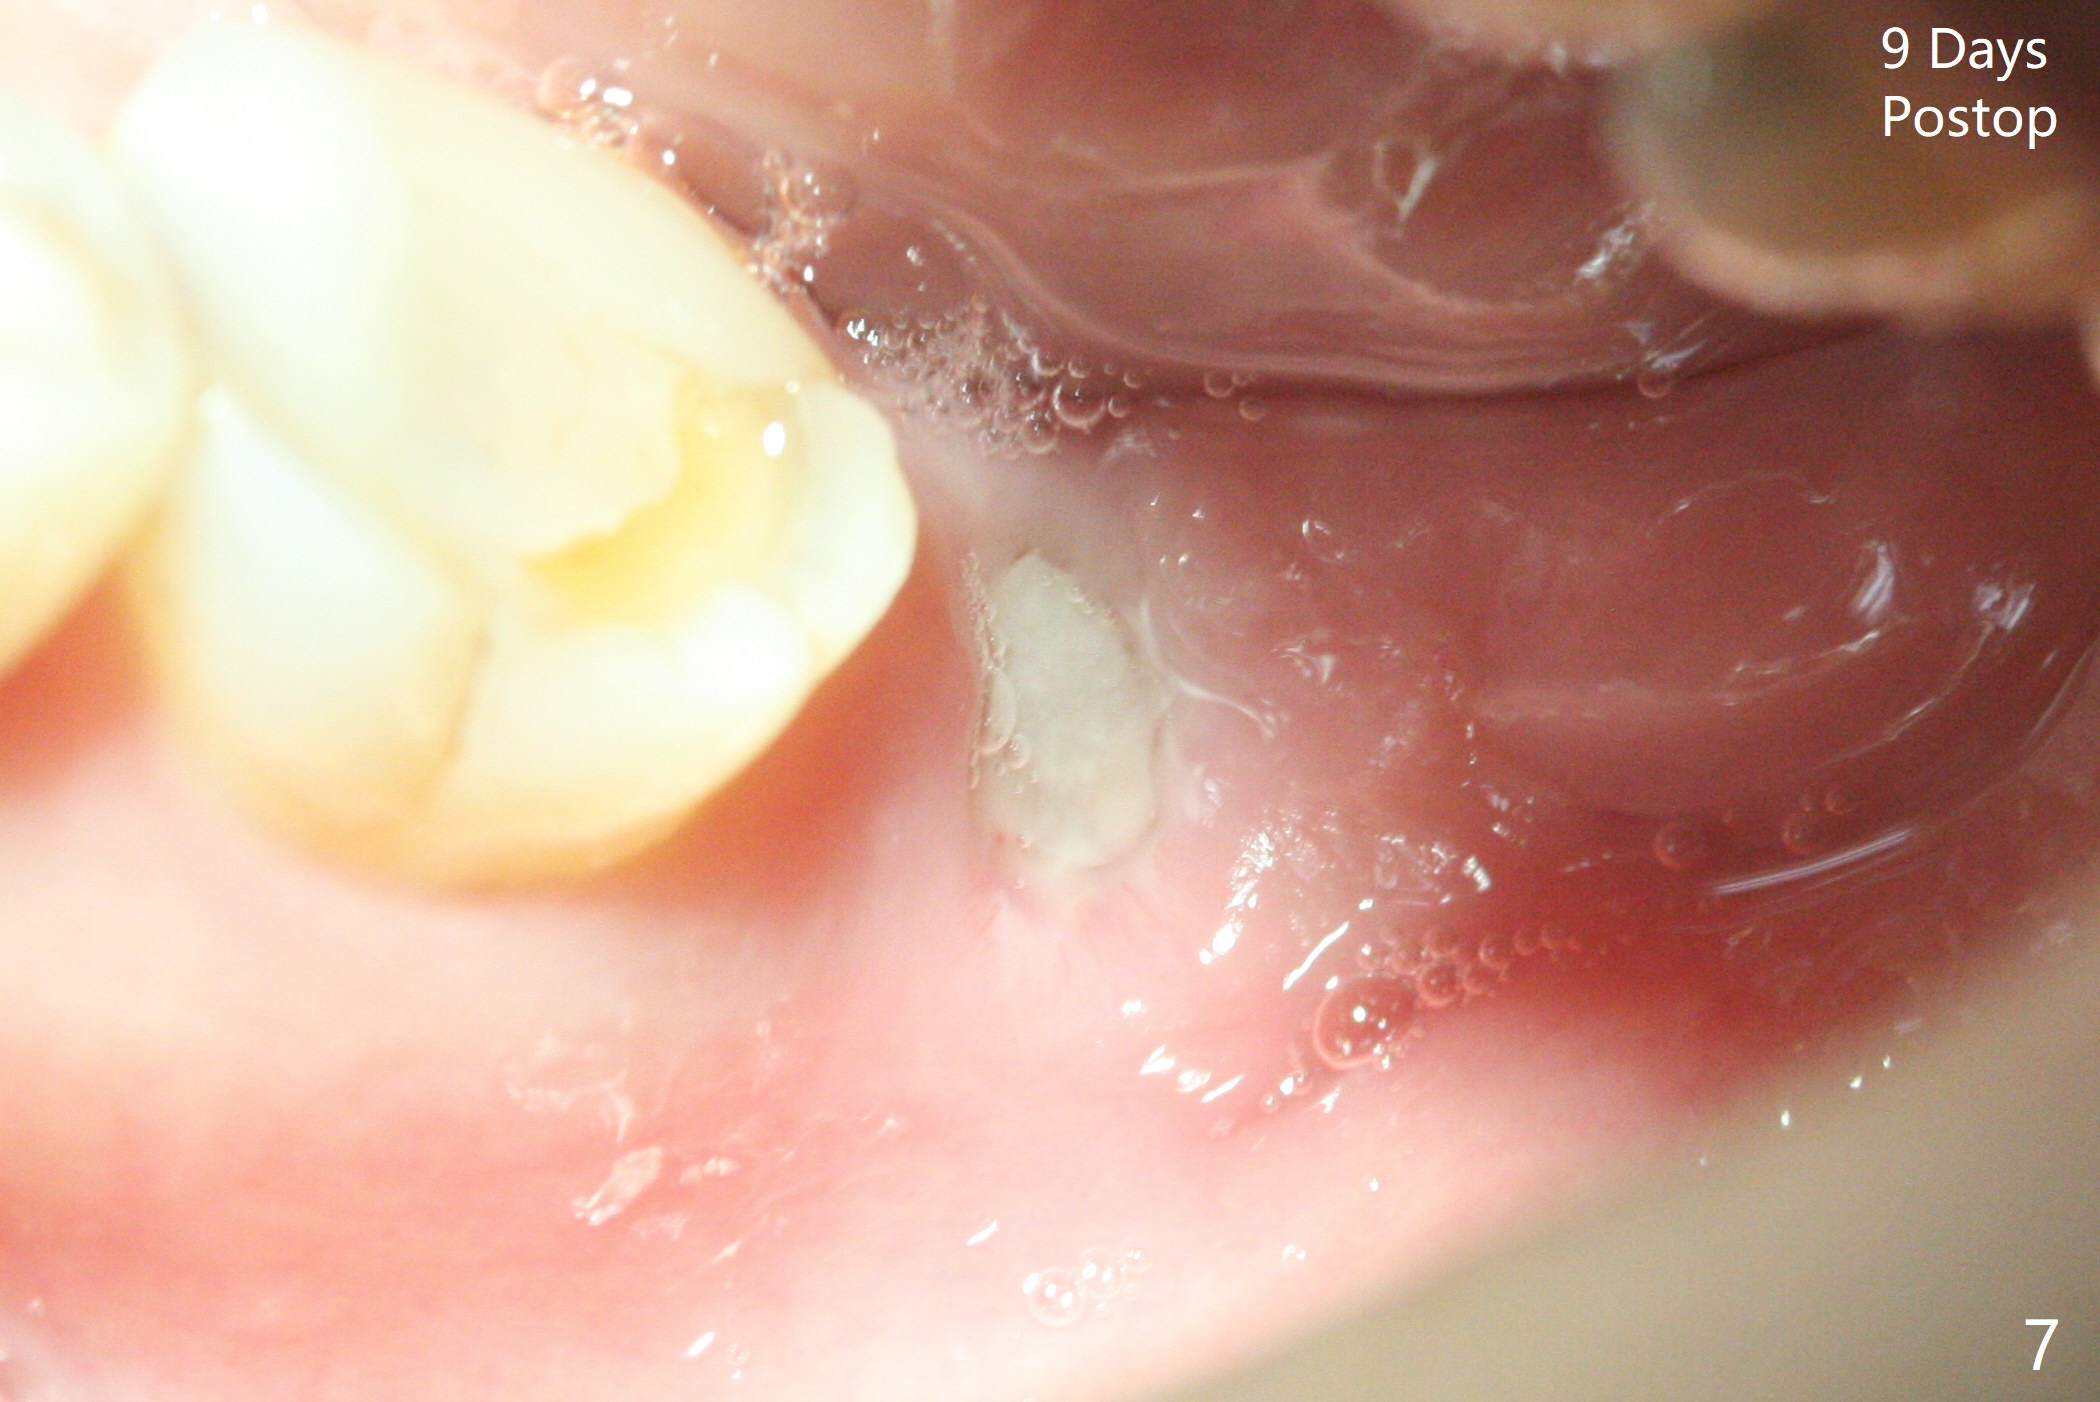

术前CT(图四):S:中隔。骨质密度低,拔牙时没植骨。植体容易进入近中牙槽窝。植牙设计:主要植入近中窝(图五),但是实际更近中。由于扭力低(骨质密度低),使用愈合螺帽,放置自体骨和胶原膜(C,GEM Cap),用牙周胶水固定(蓝色,图六)。胶原膜术后九天好像仍在原位(图七)。术后3个月牙槽嵴粘膜愈合正常,翻瓣后必须用钻头去除愈合螺帽冠方骨质,植体周围骨质密度增加(图八)。修复基台仿佛没有与牙槽嵴接触(图九)。调整基台高度后,取模。最后使用树脂水门汀。